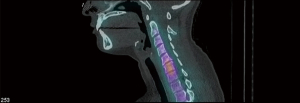

The patient was identified on physical examination to have diminished sensation in the right fourth and fifth finger (C8) and the left shoulder, radial aspect of forearm, thumb, index finger, and middle finger (C5 and C6). The reflex examination was 2+ throughout except for the left biceps and triceps which were 3+. The patient had 5/5 strength in all muscle groups in the upper and lower extremities. There was tenderness of the paraspinal musculature posteriorly. The patient had limited range of motion on account of pain in the neck. Patient was determined to have cervical disc disease with disk disease associated with C5–C6 and C6–C7 (Figures 1,2).

Figure 1 T2 sagittal magnetic resonance imaging demonstrating herniated disc of C5–C6 and C6–C7.

Figure 2 Pre-operative spectrometry scan identifying disc disease of C5–C6 and C6–C7 vertebrae.